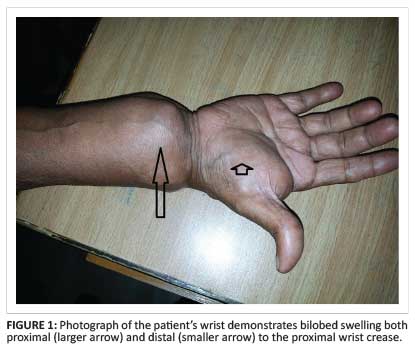

A 70-year-old man, a farmer by profession, presented with swelling in the volar aspect of his right wrist with associated dull aching pain for 6 months. Tingling and numbness was present in the volar aspect of the wrist and the ring and little fingers. There was associated history of evening pyrexia and weight loss. On examination, an hour-glass swelling above and below the proximal palmar crease (Figure 1), with a positive cross-fluctuation test, was noted. Blood parameters were within normal limits except for a high erythrocyte sedimentation rate (ESR) of 70 mm/hr in the first hour.